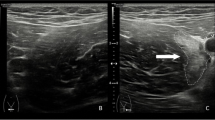

Connell and others showed a correlation between the length of the lesion on ultrasonography and recovery time, while Petersen and others argued that there was no correlation with the extent of the lesion and that there were no differences in prognosis between players that showed ultrasonography abnormalities and those who had a normal ultrasound examination (Fig. 2) [15, 23].

a 24-year-old athlete with type 2 muscle tear (Peetrons). The alteration of the echostructure involves the proximal myotendinous junction of the femoral biceps muscle and is characterized by a small interruption in the continuity of the fibers (arrow); b 22-year-old athlete with type 2 muscle tear (Peetrons). The US examination illustrates a small myofascial lesion (arrow) in the rectus femoris